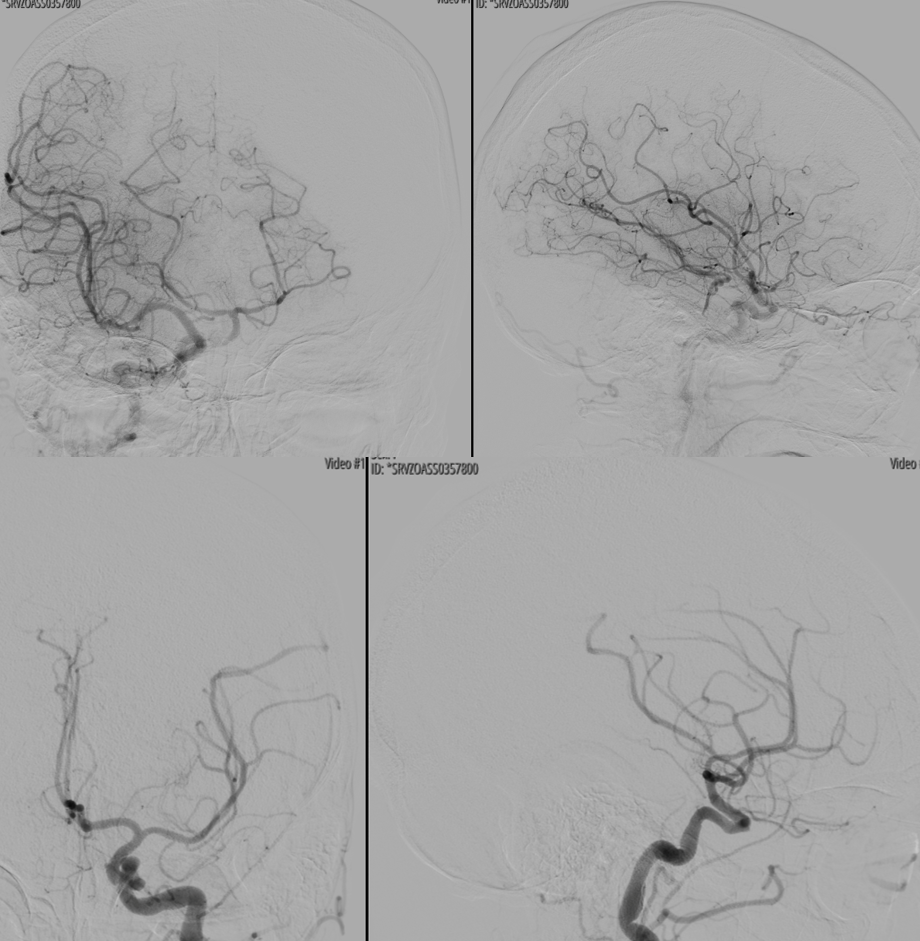

Vaso-CT (22 cm FOV protocol, 20 seconds acquisition, 50% contrast manual injection – 250 mg/ml, reconstructed with 50% FOV and 5123 matrix). We can see a stenosis at the origin of the PICA due to snowplough effect of the inflated balloon on the plaque — this is quite acceptable. With complete coverage of the PICA the result could be bad indeed. Precision matters a lot.